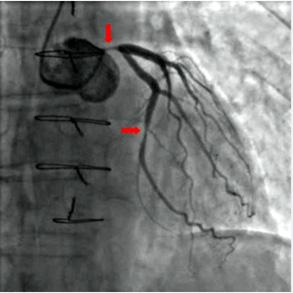

Como se ha reiterado en varias ocasiones, el diagnóstico del SCACEST ha de ser rápido para instaurar lo antes posible la terapia de reperfusión y disminuir el tamaño del infarto. Por ello, se tiene que basar en la historia clínica del paciente y en el ECG. Ya he mencionado con anterioridad que el ECG debe realizarse en menos de 10 minutos tras el primer contacto médico del paciente3. Los criterios electrocardiográficos diagnósticos de SCACEST son los siguientes1,3. Por un lado está la elevación del segmento ST desde el punto J en dos derivaciones contiguas (fig. 1), con punto de corte en 0,1 mV o más en todas las derivaciones, salvo en V2-V3 (donde los puntos de corte son 0,2 mV o más en hombres de más de 40 años, 0,25 mV o más en hombres de menos de 40 años y 0,15 mV o más en mujeres). Se consideran derivaciones contiguas grupos de derivaciones como anterior (V1-V6), inferior (II, III, aVF) o lateral (DI y AVL).

5. ECG sugestivo de lesión de tronco coronario izquierdo. Se caracteriza por un descenso generalizado del ST en todas las derivaciones, salvo aVR, en la que existe ascenso del ST (fig. 2) 1,5.

Existen dos estrategias de reperfusión para el SCACEST, una es la angioplastia primaria que es la estrategia preferida de reperfusión siempre que se pueda llevar a cabo en unos tiempos determinados, y que consiste en realizar coronariografía urgente, descubrir la arteria responsable del infarto y llevar a cabo una revascularización percutánea para restablecer el flujo a través de la coronaria obstruida. La segunda es la fibrinolisis que consiste en la administración intravenosa de un fármaco que lisa el trombo.